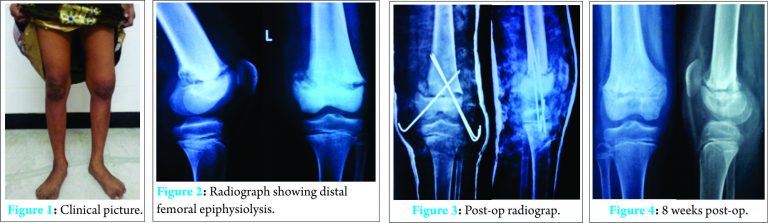

A 12-year-old girl child came with complaints of limp while walking and swelling in the left knee for past 5 weeks (Fig. 1: clinical picture). Mother gave history that the girl is a known case of congenital insensitivity to pain with clear history of no pain on intramuscular injection since birth. The diagnosis was made by our senior neurophysician on the basis of clinical examination and findings of sensory and motor system. The diagnosis of congenital insensitivity to pain is done by positive family history and characteristic symptoms. Nerve conduction studies and EMG has no role in diagnosis of this condition and it was not recommended in this child by our neurophysician. Genetic studies were not done, as it only reflects the way of inheritance and will not add to the diagnosis, but were advised to the parents while counselling. She had no significant trauma, fever, other joint involvement or any features of rheumatism. Physical examination of the skin, nails, heart and lungs were unremarkable. On local examination, she had no bony tenderness, mild warmth, and moderate knee effusion. Range of movement was terminally restricted, with normal distal pulse, power and deep tendon reflex. Pin prick sensation was normal. Plain radiograph showed epiphysiolysis of distal femur with widening of physis (Fig. 2: radiograph showing distal femoral epiphysiolysis). Knee aspirated in emergency department showed straw coloured synovial fluid. Synovial fluid analysis for microscopic and biochemical parameters were normal. Blood tests for infection, clotting profile and arthritis profile markers were normal. Examination under anaesthesia demonstrated gross movement at physis on varus, valgus stress views under fluoroscopy guidance indicating lower femoral physeal separation. This unstable distal femoral epiphysis was treated under general anaesthesia with closed reduction, percutaneous cross pinning [2] and above knee plaster cast (Fig. 3: post-op radiograph). After 8 weeks (Fig. 4: 8 weeks post-op radiograph), the pins were removed in emergency department and knee range of motion exercises started. Twelve weeks follow-up showed complete disappearance of swelling around the knee and child could walk normally with no limp. Radiograph showed increased radio-opacity (healing) at physis. As a measure of prevention of further fractures, we advised her to use preventive splints during any vigorous activity. At 1-year follow-up, the patient was perfectly normal with no signs and symptoms around knee and normal physeal growth.